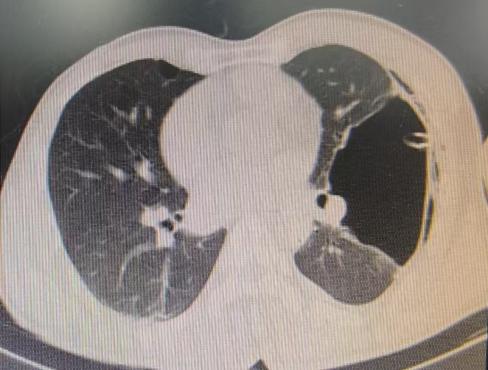

患者信息及手术操作:38岁的李先生(化名)最近总算松了一口气。多年来一直困扰他的左肺巨大肺大疱(76mm×117mm),在我院呼吸与危重症医学科专家团队的精心医治下,通过微创手术得到了显著改善。

近期,国内知名呼吸介入专家陈愉教授联合我院呼吸与危重症医学科团队,为李先生施行“胸腔镜下肺大疱探查术 + 胸腔闭式引流术”。手术中,陈愉教授运用单孔胸腔镜技术,仅在患者胸壁开了一个1cm的小切口。通过高清胸腔镜系统探查发现,患者胸腔内存在广泛粘连以及多发微小肺大疱,肺叶解剖结构异常,肺门血管直接暴露,经判断肺大疱腔已与胸腔贯通。

面对这一复杂状况,陈教授凭借丰富的经验果断调整手术方案。在确保安全的前提下,对可疑病灶进行了精准活检取样,随后精准置入胸腔引流管。术后即刻CT确认引流管位置良好,同时制定了严密的术后管理方案:每日监测引流量及肺复张情况,若引流量持续减少且肺大疱逐渐缩小,则按计划拨管;若肺大疱未明显缩小,则考虑拔除引流管后转外科进行胸膜剥离术。

术后复查CT显示,肺大疱明显缩小,患者胸闷症状显著减轻。整个手术过程进展顺利,患者术后恢复良好。

(术前左肺肺大疱明显-术后肺大疱逐渐缩小闭合)